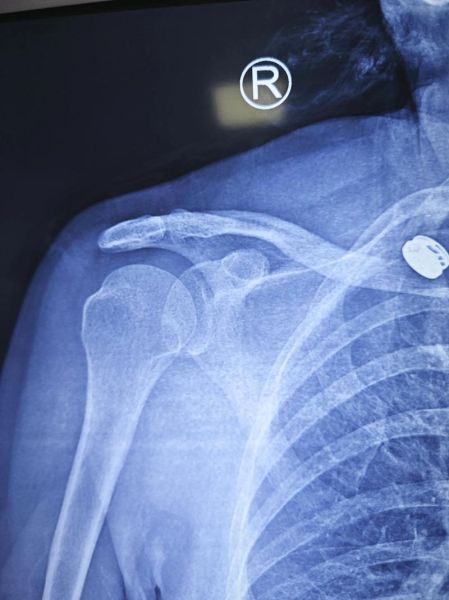

3. 肩部轮廓轻微不对称 肉眼可见患侧肩峰(肩膀最高点)比另一侧略突出,或出现小凹陷,但肿胀不一定明显。

Q2:脱臼和骨折怎么区分?

骨折通常伴随:

- 明显肿胀或瘀青

- 局部骨擦音

- 拒绝任何方向的活动

而脱臼多表现为特定姿势固定、被动活动尚可但疼痛加剧。最保险的做法仍是去医院拍片排除骨折。